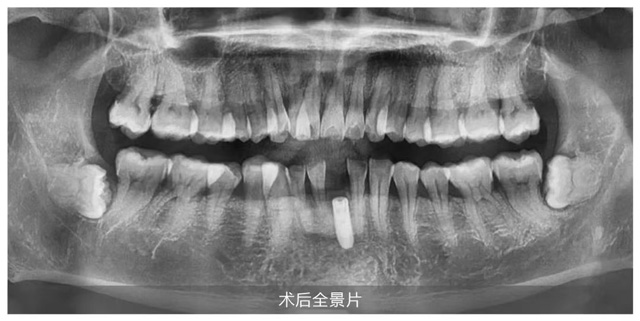

上午10:43时,随着王锋总监娴熟实施麻醉、备洞、植入等关键步骤,手术在短短15分钟内完美收官,全程无痛、出血量少,充分展现了数字化种植的微创优势。直播顾客王先生十分满意地表示:“手术全程不紧张,也没有痛的感觉。医生的技术和新桥口腔整体服务都超出了我的期待。”